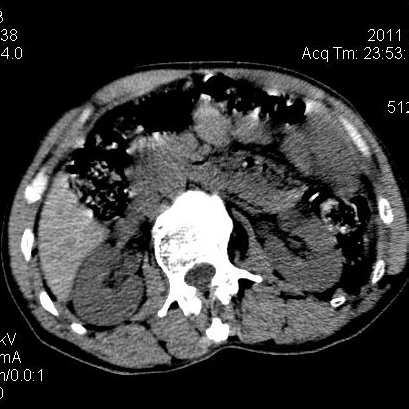

肝左叶发育异常

男性,55岁,骑摩托车摔倒后入院,自述右上腹疼痛

[backcolor=#FF0000]第一次诊断的时候也是这么肯定,可是床旁超声检查并没有发现明显异常,而且患者的一般症状都良好。还好临床只是保守治疗,没有立即手术,第二次复查的时候没有一点变化,又做了MRI检查,没有血肿,

这是一例肝左叶发育异常的,很个性吧~[/backcolor]